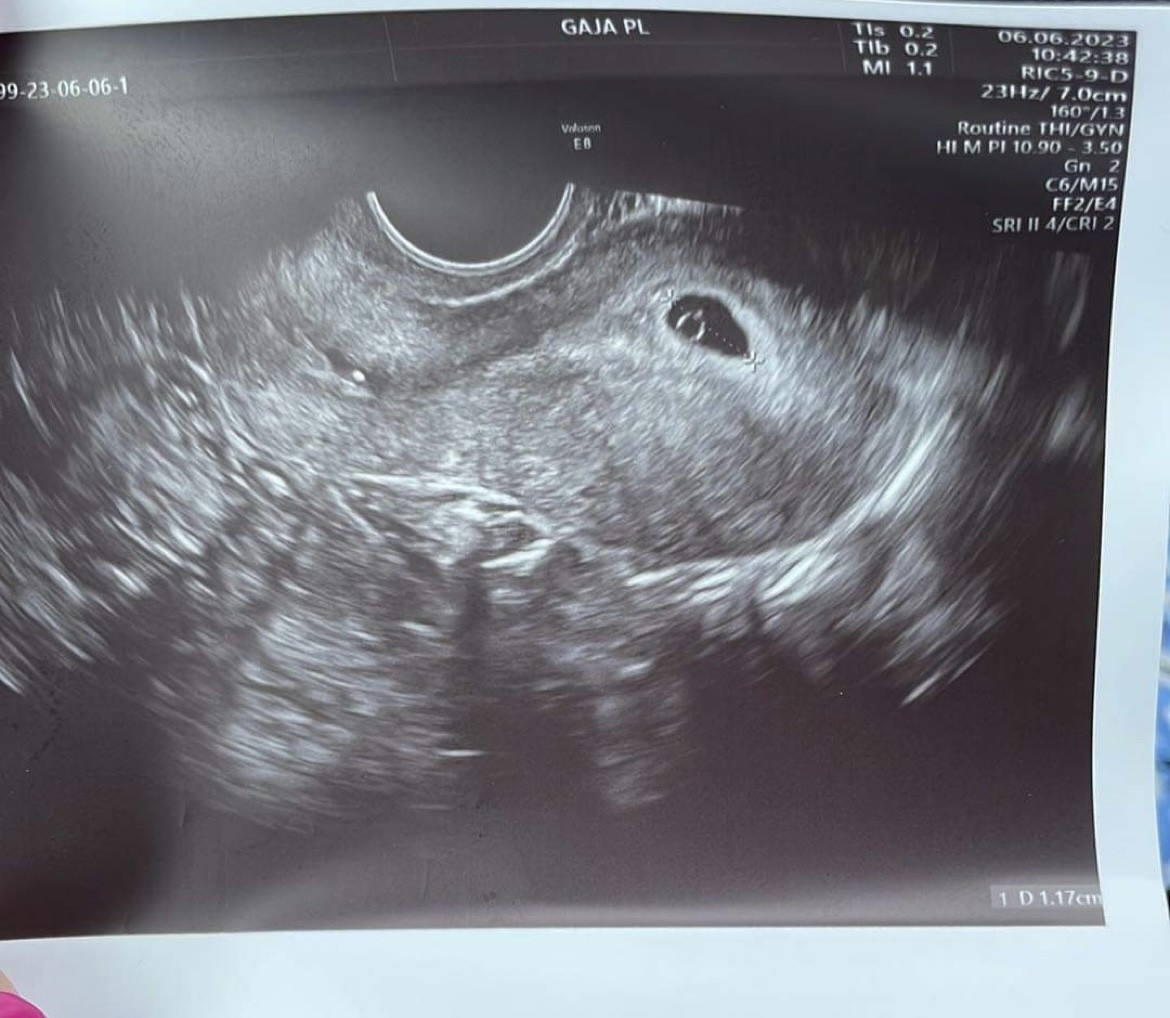

We wtorek dowiedziałam się, że jestem w ciąży według ostatniej miesiączki 6 tydzień (5t2d), na USG widać pęcherzyk ciążowy No właśnie i co? Ciałko żółtkowe?

Lekarz powiedział tylko, że jest dobrze jak na tym etapie i mam przyjść za 2 tygodnie to założymy kartę ciąży oraz dał skierowanie na badania.

Wynik bety jaki otrzymałam w ten, że wtorek to 6656 mlU/ml - lekarz nic nie mówił o powtórzeniu.

Jak na wynik bety to obraz prawidłowy, że Ci nie kazał powtarzać to ok, teraz już nie przyrasta tak szybko beta. Czekaj na wizytę, będzie widać więcej. ;)